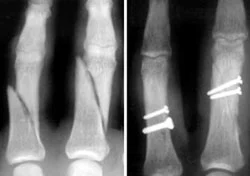

Metacarpal Fractures

- Careful about rotational malalignment

- Check rotation by flexing the fingers

- Undisplaced / or only one MC

- Treatment by cast / or splint

- Displaced / Rotated / Multiple

- Treated by internal fixation (screws / plates / wires)